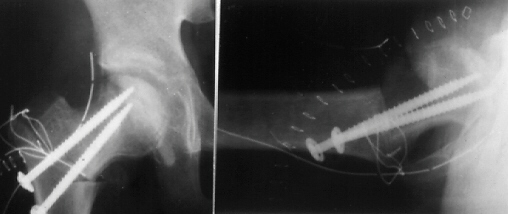

K.B.. 12-year-old boy. B.W. 63 kg(139 Ib.) . Perthes disease.

He had right hip pain and limping for seven weeks. When he was

first seen at University Hospital of Niigata, the right femoral

head was deformed already and collapsed slightly on X-ray.

The lateral part of the femoral head showed an impingement lesion.

Because good sphericity of the posterior part of the femoral head

was still preserved,

Sugioka's rotational osteotomy was advised. Pre-operative range

of motion was flex.90, abd.35, e.r. 40, and i.r. 15. The femoral

head was anteriorly rotated by 75 degrees and varus angulation

by 15 degrees was made.

Continuous-passive-motion and pulley exercise on a bed was started

from the 1st post-operative day. Skin traction was performed for

2 weeks. After post-operative non-weight-bearing for 4 weeks,

and partial-weight-bearing for 6 weeks, he has had neither limping

nor pain for more than 3 years.